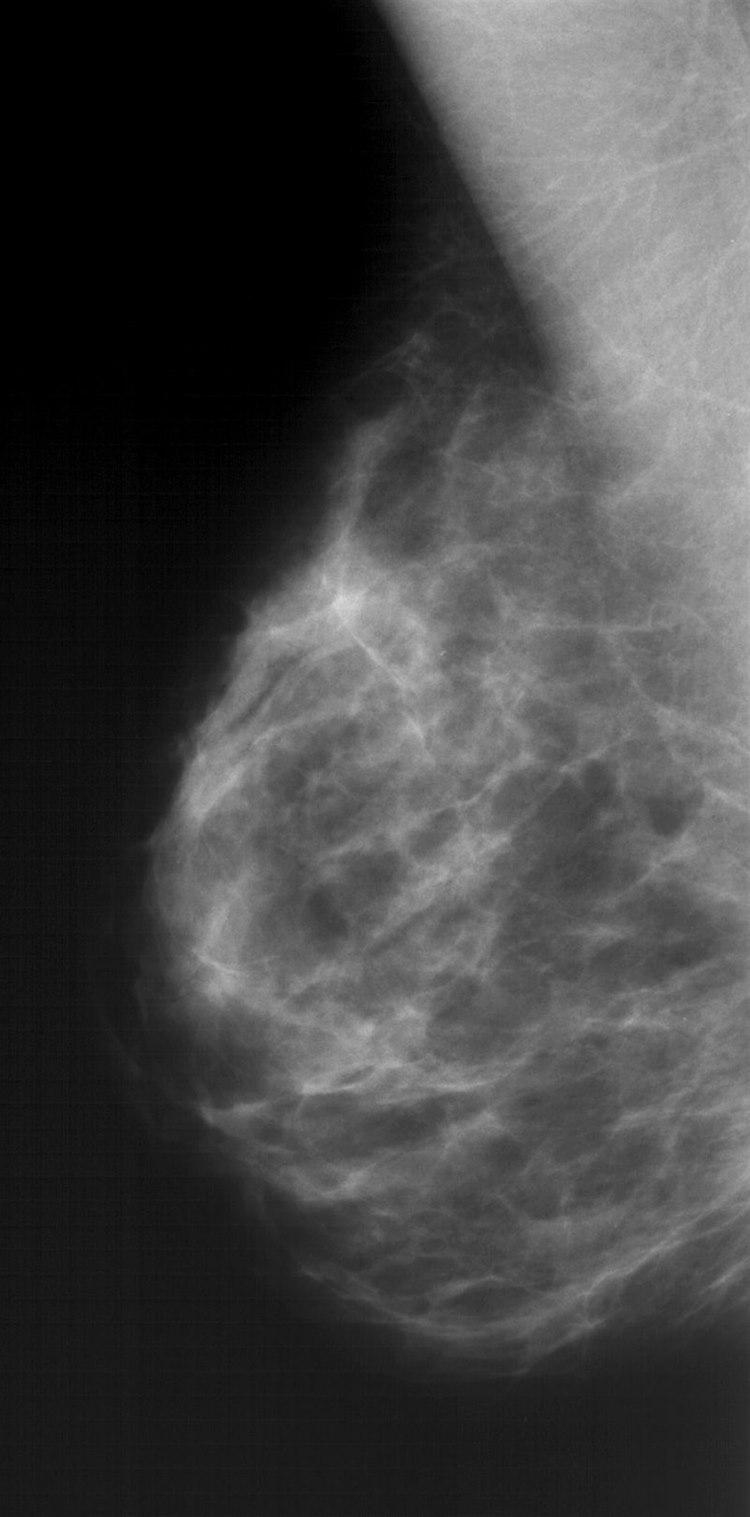

Mammografi er en røntgenundersøkelse som framstiller brystvevet slik at forandringer som kan være uttrykk for brystkreft, lar seg avbilde. Kreftsvulster mindre enn én centimeter kan vanligvis ikke påvises ved rutinemessig undersøkelse av brystene utført av kvinnen selv eller legen. Det er liten strålefare med undersøkelsen.

Det normale brystvevet endres med alderen fordi kjertelvev etter hvert forsvinner og fettmengden øker. Det er stor variasjon i det mammografiske utseende av normale bryst. De fleste ondartede forandringer kan påvises ved mammografi, men som ved andre diagnostiske undersøkelser hender det at noe overses eller ikke er synlig på bildene.

Røntgenbildet viser kjertler, melkeganger og bindevev mot en bakgrunn av fett. Ved typiske forandringer kan røntgenlegen skille godartet fra ondartet forandring. Mens godartede forandringer skyver normalt brystvev tilside når de vokser, kan ondartede forandringer vokse inn i omliggende brystvev. Utseende av svulsten og forkalkninger kan også gi viktig tilleggsinformasjon. Tidligere røntgenbilder av brystene er verdifulle til sammenligning når røntgenlegen vurderer de nye bildene. Supplerende ultralyd kan være avklarende, og gjøres vanligvis der det er unormale funn på mammografi. Hos noen tas en nåleprøve fra vevet i den mistenkelige forandringer for endelig avklaring.

Godartede fortetninger som cyster og bindevevsknuter (fibroadenomer) er vanligvis runde og klart avgrensede. Ondartede fortetninger er vanligvis uregelmessige med uklar avgrensning og innvekst i omgivende vev, ofte med økt antall blodkar. Forkalkninger kan ses som små spredte saltkorn (mikrokalsifikasjoner), og enkelte typer forkalkninger kan være uttrykk for kreftsvulst. Sannsynligheten for at det er ondartet, øker når forkalkningene er samlet. Forskyvning av tilgrensende brystvev og fortykkelse av hud kan også være krefttegn. En del forandringer i brystvevet kan være vanskelige å fortolke og krever tilleggsundersøkelser.